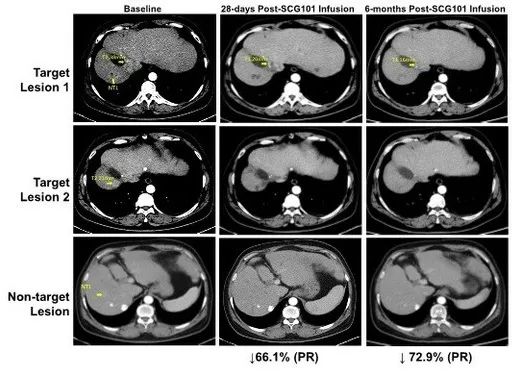

2023年6月,国际细胞与基因治疗大会(ISCT)上公布了SCG101的突破性临床数据。本次临床试验有一例乙型肝炎病毒(HBV)相关肝细胞癌(HCC)患者入组,入组后给予单剂SCG101输注治疗,且未接受其他抗肿瘤治疗,治疗结果如下:

1、肿瘤缓解:患者在治疗第28天,肿瘤靶病灶比基线缩小66%,达到部分缓解(PR);并在治疗第4个月时,病灶进一步缩小74.5%;另一处病灶则完全消失。截至数据统计时,该患者仍处于持续缓解状态,肿瘤未进展时间>6.9个月。

图2 HBV相关肝细胞癌患者,回输SCG101前后影像学变化

▲图源“CISION”,版权归原作者所有,如无意中侵犯了知识产权,请联系我们删除